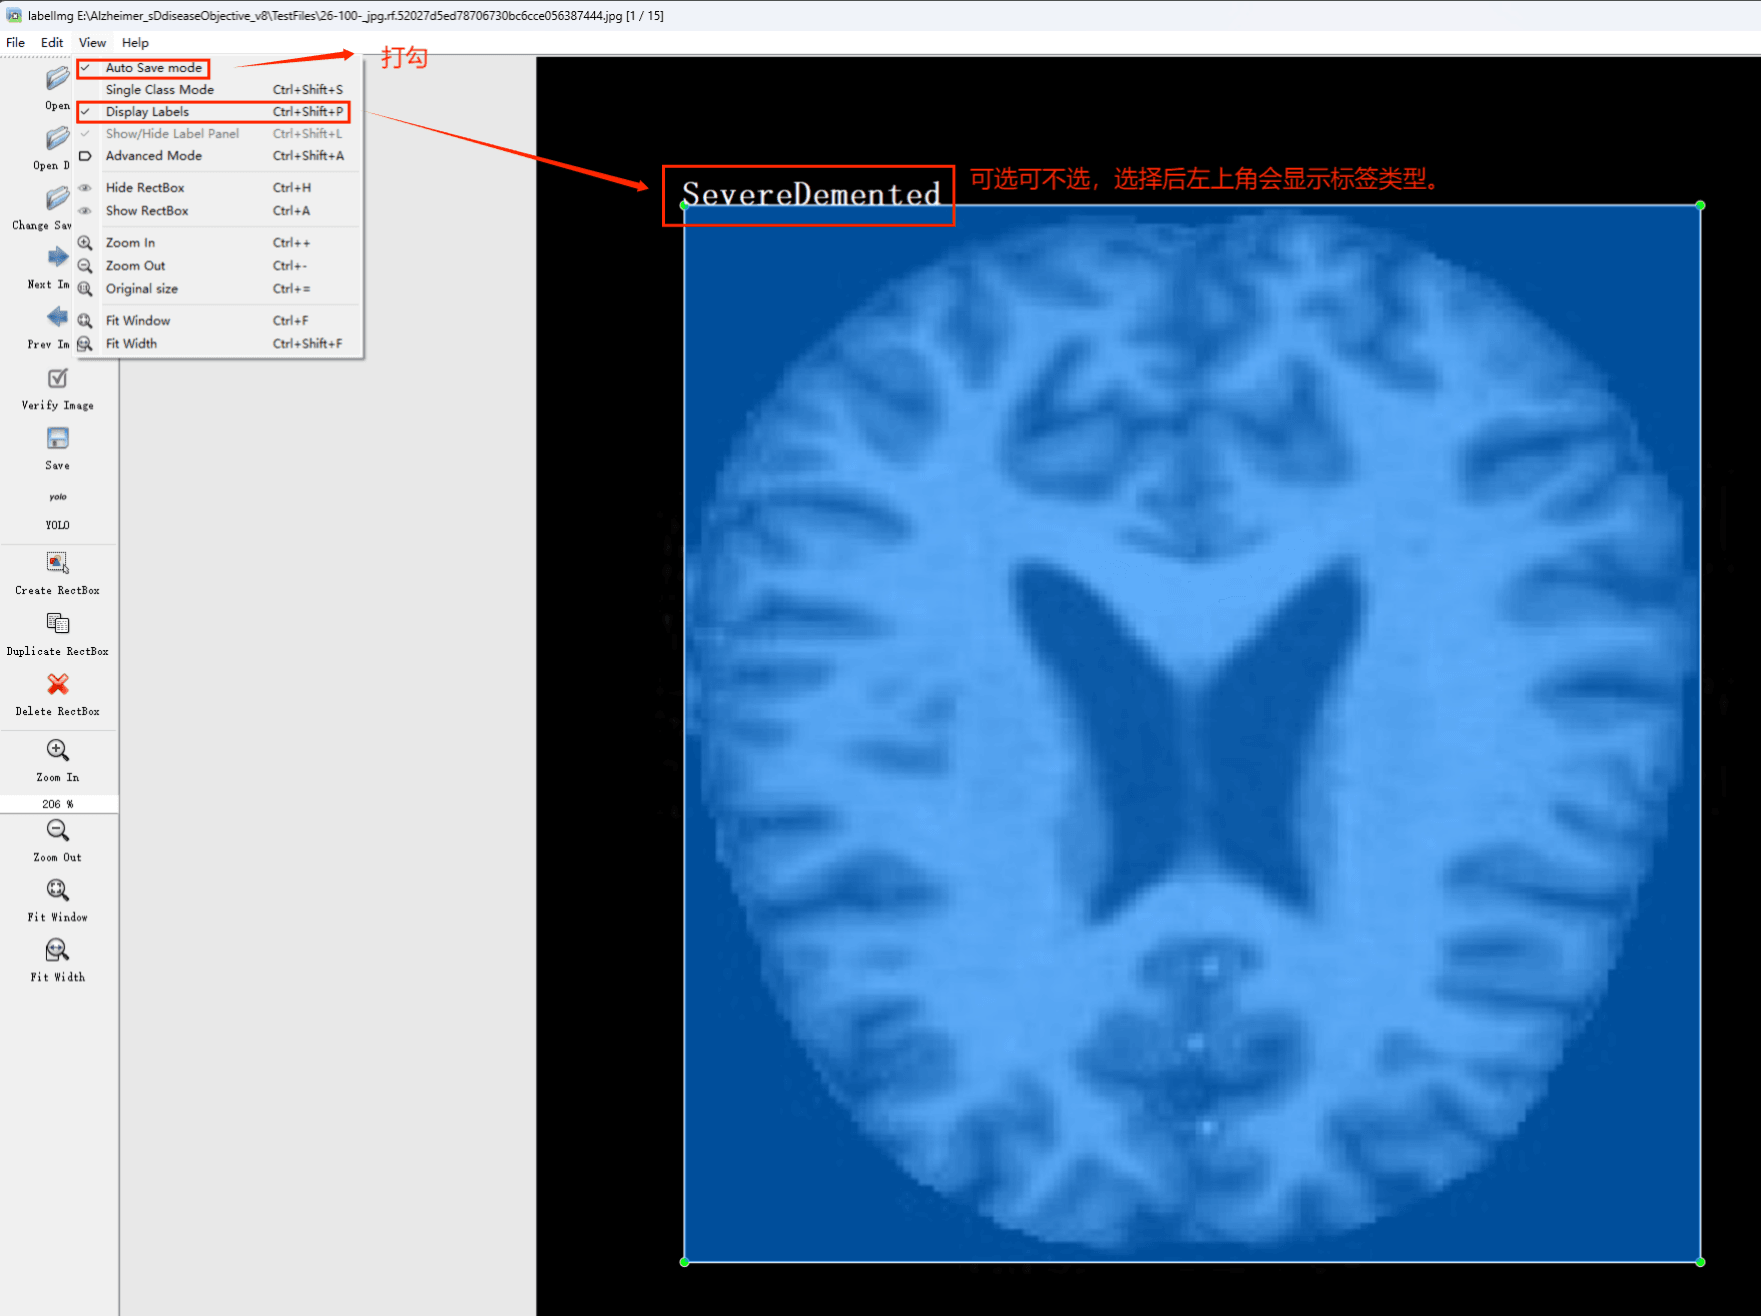

Tipps:通过搜集关于数据集为各种各样的老年痴呆症相关图像,并使用Labelimg标注工具对每张图片进行标注,分4个检测类别,分别是”SevereDemented”,”VeryMildDemented”,”MildDemented”,”NonDemented”,”ModerateDemented”。

目标检测标注工具

(1)labelimg:开源的图像标注工具,标签可用于分类和目标检测,它是用python写的,并使用Qt作为其图形界面,简单好用(虽然是英文版的)。其注释以 PASCAL VOC格式保存为XML文件,这是ImageNet使用的格式。此外,它还支持 COCO数据集格式。

(2)安装labelimg 在cmd输入以下命令 pip install labelimg -i https://pypi.tuna.tsinghua.edu.cn/simple

初识labelimg

打开后,我们自己设置一下

在View中勾选Auto Save mode

接下来我们打开需要标注的图片文件夹

并设置标注文件保存的目录(上图中的Change Save Dir)

接下来就开始标注,画框,标记目标的label,然后d切换到下一张继续标注,不断重复重复。